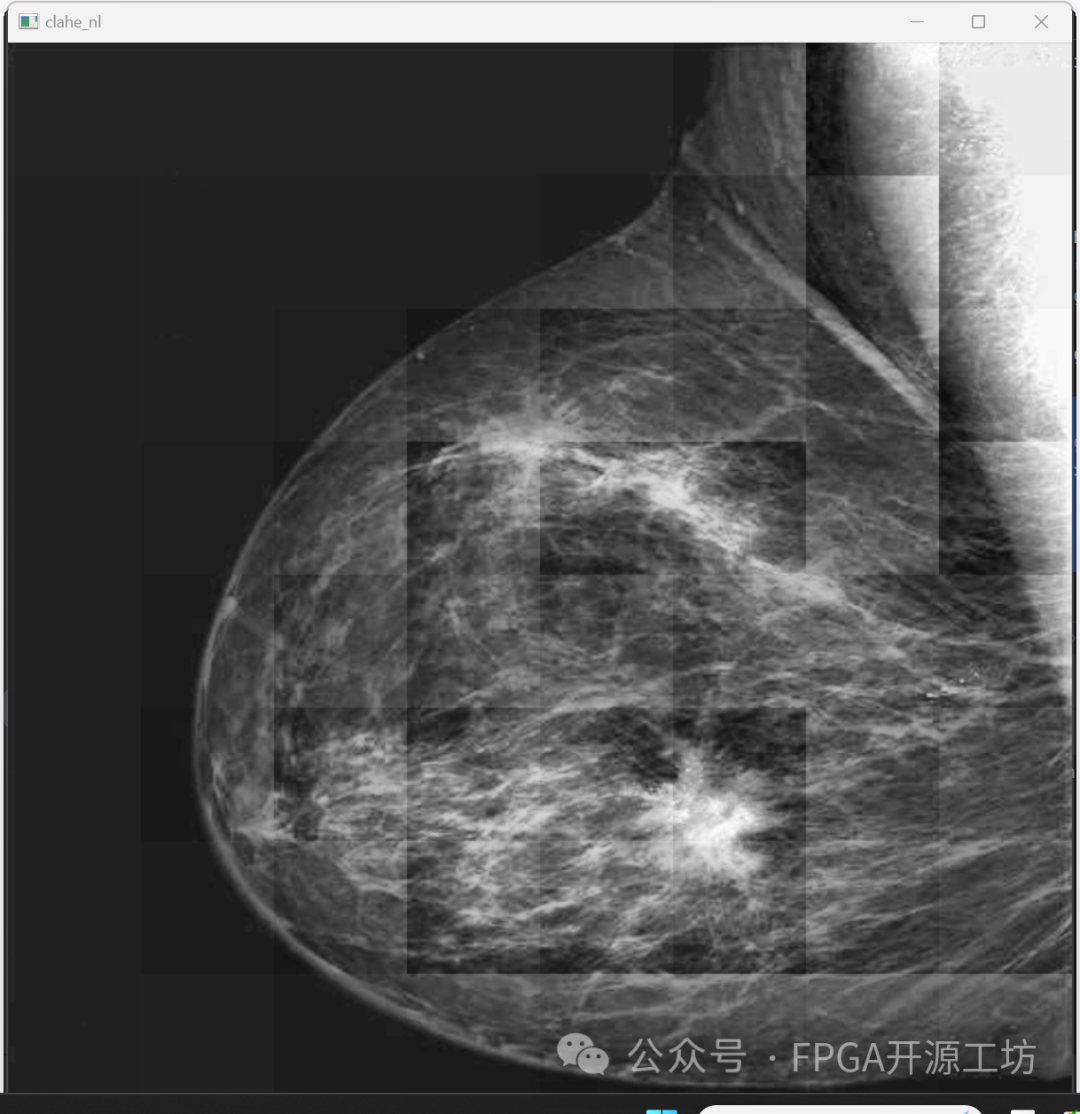

来看一下最后的效果:

可以看到相对于没有进行限制对比度的效果要好很多。

下面这幅图是没有限制对比度阈值的结果: